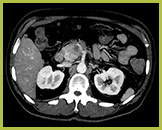

Badanie wykonane metodą „Iodine no H20”

Zapewnia lepszą wizualizację tkanek wzmocnionych kontrastem na bazie jodu. Wynik pozwala na dokładną ocenę ilościową jodu w mg/ml.